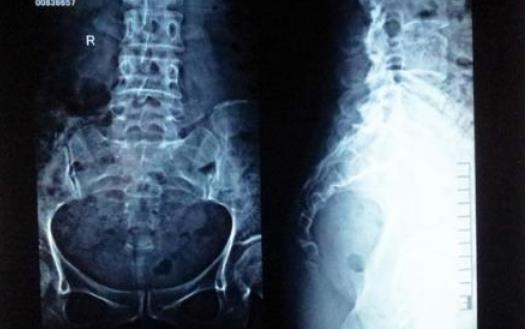

尾骨其實(shí)就是人類的“尾巴”,隨著人類的進(jìn)化,尾巴的作用越來越小,最終“退化”到如今的結(jié)構(gòu),看起來像是三角形。由于生理結(jié)構(gòu)的不同,女性尾骨比男性的更小、更低一些,所受壓力更大,因而女性更容易出現(xiàn)尾骨疼痛。

除了慢性勞損,外傷、退行性病變、盆腔疾病甚至腫瘤等原因都可能引發(fā)尾骨疼痛。坦言,針對長期勞損甚至韌帶鈣化引起的尾椎疼痛,傳統(tǒng)的藥物治療、熱敷等效果往往不佳,原因是患處解剖位置比較特殊,患者比較難依從。借助沖擊波治療尾椎痛,因?yàn)橹委煏r(shí)間短,患者依從性提高,效果緩解十分明顯。尾椎疼痛比較嚴(yán)重時(shí),可以嘗試使用中間鏤空的坐墊,避免尾骨受到椅面擠壓而疼痛加劇。